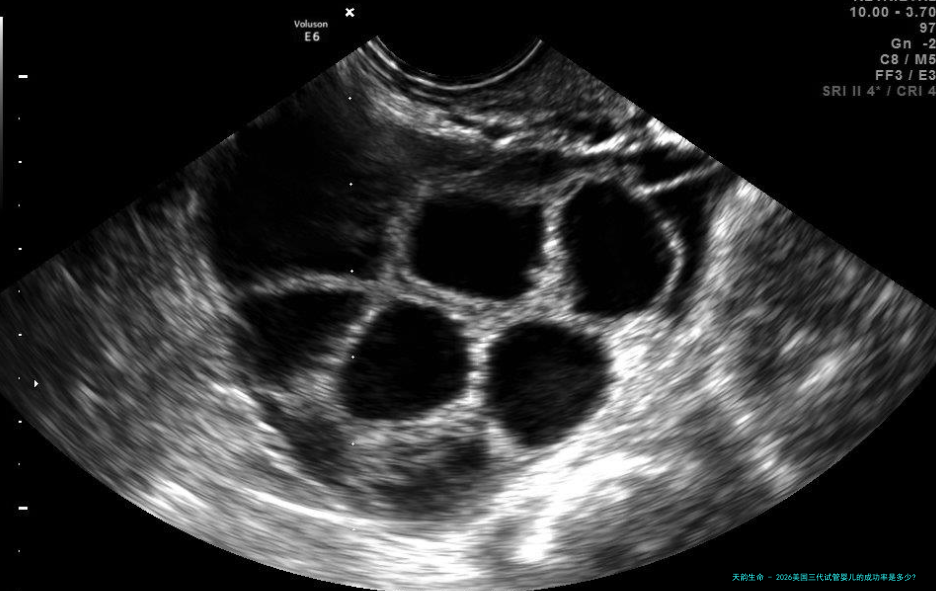

美国三代试管婴儿的成功率是几许?试管婴儿的费用是几何?三代试管婴儿成功率是不是高是每一个三代试管婴儿家庭都耽忧的问题。然而,跟着三代试管婴儿技术的不断发展和前行,三代试管婴儿的成功率变得比先前更高。固然增加幅度很大,但三代试管婴儿受作为一种医疗步骤有可能失败。我们来瞧瞧美国三代试管婴儿的成功率。多高?

愈来愈多的人去美国做三代试管婴儿手术。根据网上数据,美国三代试管婴儿的成功率在70%左右,怎样才能高三代试管婴儿的成功率呢?羊毛?